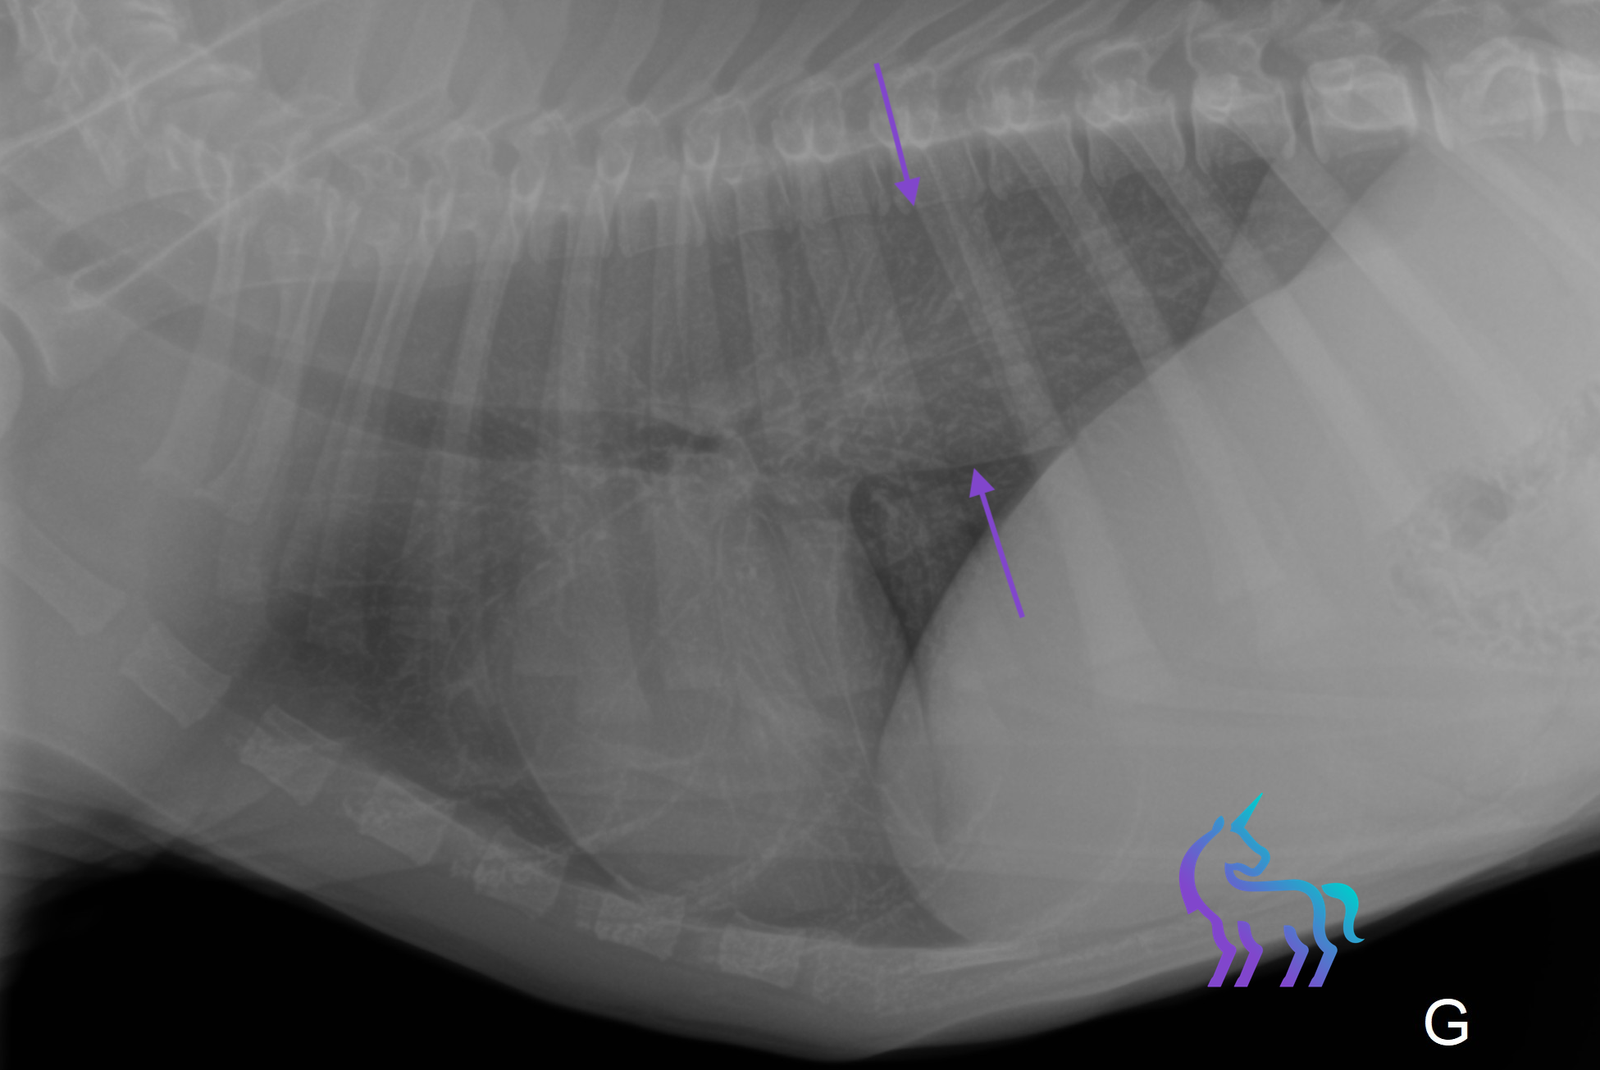

Identification d’une masse pulmonaire du lobe caudal droit

Espèce : ChienRadiographies thoraciques montrant une masse pulmonaire unique, bien délimitée, d’environ 5 cm, située dans le lobe pulmonaire caudal droit.

L’aspect radiographique est compatible avec un carcinome pulmonaire.

Diagnostic : La radiographie permet ici de poser un diagnostic tumoral pulmonaire et d’orienter la prise en charge.